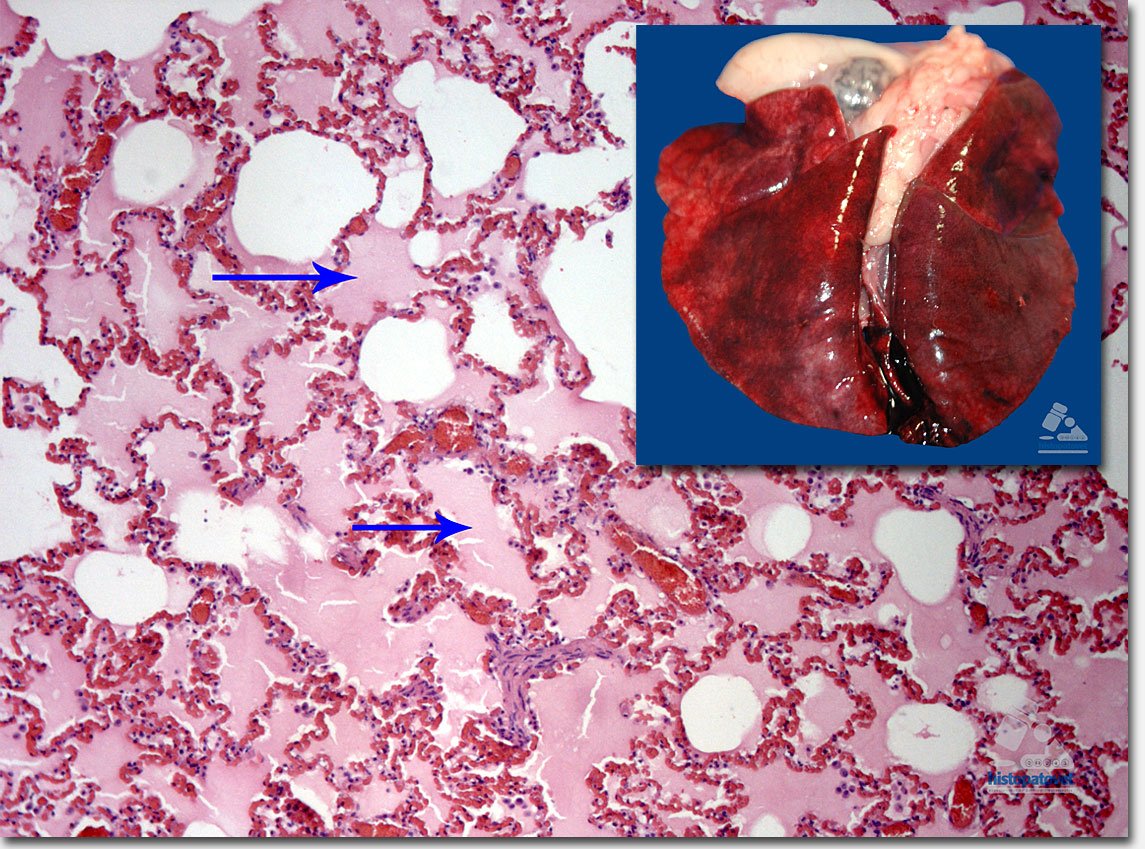

De forma difusa, los hepatocitos mostraron múltiples vacuolas vacías (lipídosis hepática). Ver las siguientes dos fotos. Las flechas muestran las vacuolas vacías.

Fig.5. De forma difusa los hepatocitos muestran las vacuolas. A la derecha un acercamiento. Causa de muerte: Insuficiencia cardio-respiratoria.

Fig. 6. Parénquima pulmonar. Las flechas señalan un material rosado dentro de los alveolos (edema pulmonar). En la parte superior el pulmón, con un aspecto rojizo difuso.